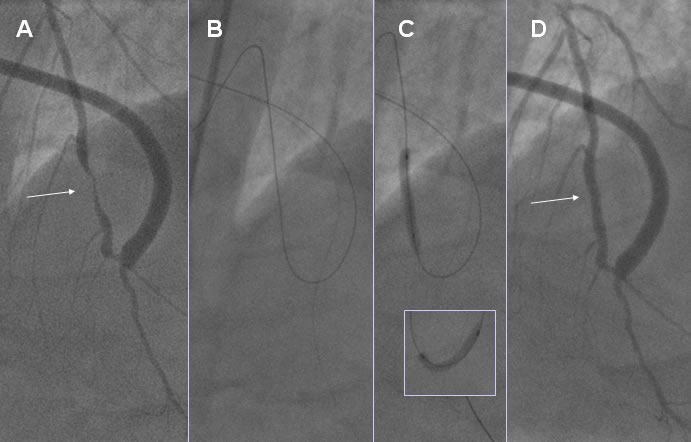

Figura 4. A, Stenosi serrata (freccia) nel tratto medio dell'arteria DA, occlusa subito dopo l'origine dal TC. Tre importanti rami settali e il primo ramo diagonale non vengono perciò sufficientemente perfusi dal graft venoso (pervio) anastomizzato nel tratto medio-distale della DA. B, un filo guida a medio supporto (BMW, Guidant) è stato fatto avanzare nel tratto distale della DA (prossimamente al tratto molto angolato da attraversare) in parallelo ad un filo guida idrofilico e più flessibile (Choice PT, Boston Sciertific) che è stato fatto avanzare in via retrograda nella DA media fino all'interno del primo ramo settale. C, angioplastica nel tratto medio della DA e sull'anastomosi del graft a livello della curva molto angolata di quasi 180°. D, Risultato finale dopo impianto di uno stent Medtronic AVE nel tratto medio della DA. In questo caso il filo guida a medio supporto ha notevolmente facilitato il successivo posizionamento in via retrograda sulla DA media del filo guida più flessibile che ha facilitato il passaggio del palloncino da angioplastica e l'impianto di stent.  |